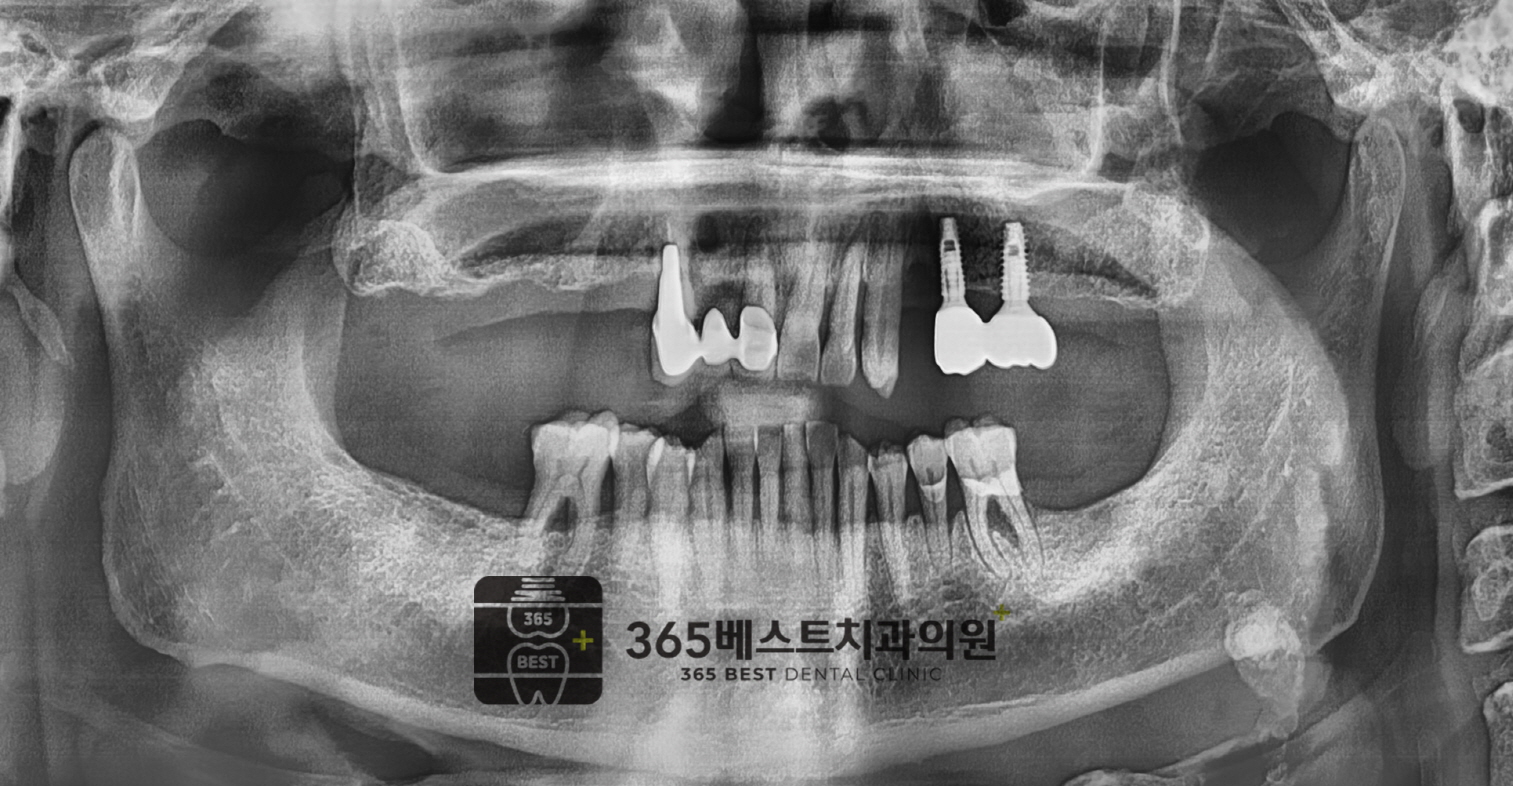

[임플란트]상악동 거상

상악동 거상/66세 남성

(후)